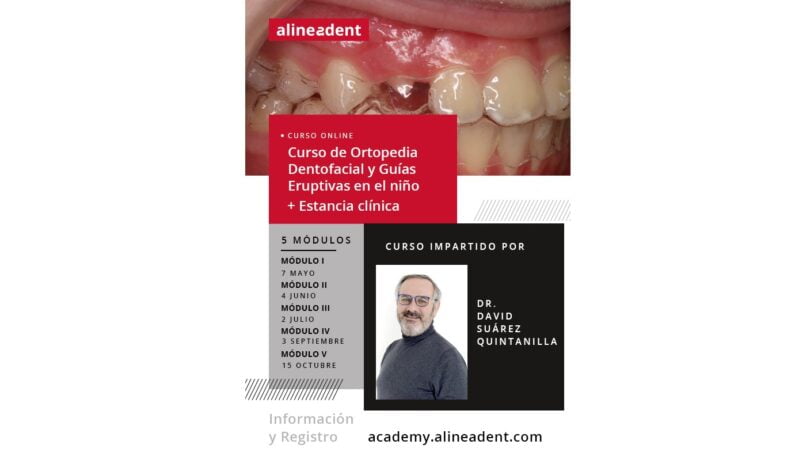

A academia europeia da Alineadent, laboratório de odontologia, juntou-se ao médico dentista David Suárez Quintanilla para levar a cabo um programa de formação de ortopedia dento-facial. Em comunicado, o laboratório revela que o programa está divido em cinco módulos e irá disponibilizar formação clínica durante três dias, em maio de 2021.

O objetivo do curso é formar os profissionais de dentária com base nos novos protocolos de diagnóstico e terapia em ortodontia infantil e adolescente, incluindo ortodontia digital funcional e alinhadores em crianças (“Guías Eruptivas Propioceptivas” – GEP). A aplicação clínica prática terá como base esses guias.

A formação pretende informar como os alinhadores, entre outros dispositivos, podem ser “uma arma terapêutica muito interessante, numa dentição mista tardia, para a correção dos problemas dentários, funcionais e de esqueleto”.

Para saber mais informações e para a inscrição pode aceder: https://academy.alineadent.com